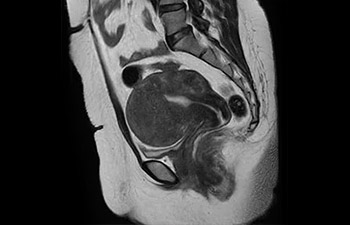

con Compressed SENSE